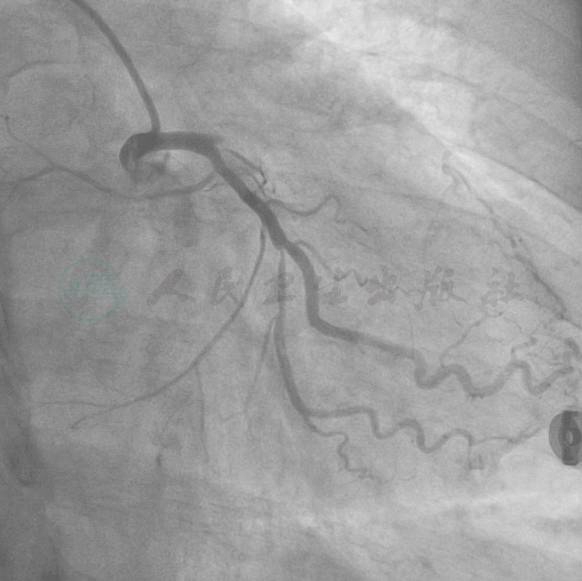

冠状动脉造影结果

选用右侧桡动脉径路,6F血管鞘。造影发现(图1~图3):左主干未见明显狭窄或阻塞性改变,前降支起始部100%闭塞,远端可见来自回旋支侧支循环。回旋支近中段弥漫性病变,狭窄最重90%。右冠状动脉:近段100%闭塞。

图1 右冠造影

图2 左冠造影1

图3 左冠造影2